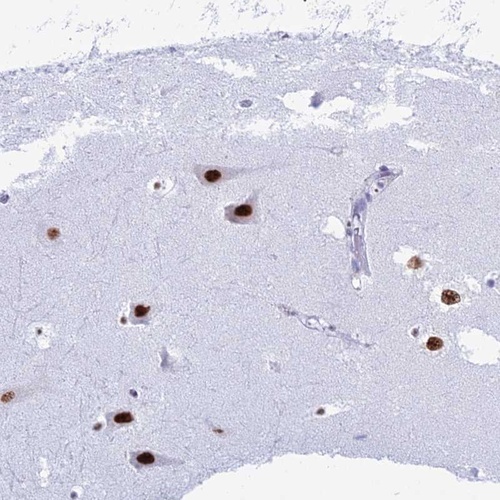

Immunohistochemical staining of human hippocampus shows strong nuclear positivity in neuronal cells.